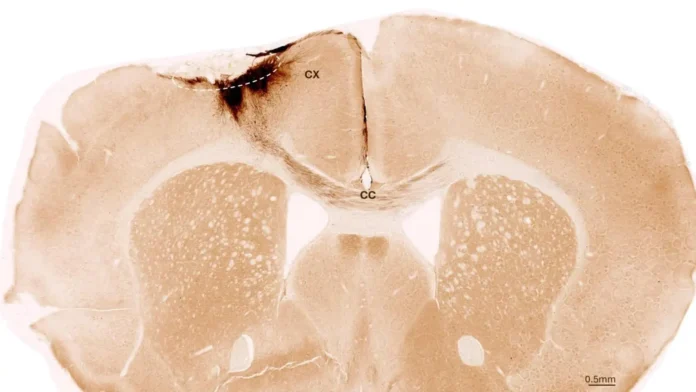

Спустя неделю после инсульта ученые ввели стволовые клетки в поврежденный участок мозга. Применяя комплекс визуализирующих и биохимических методов, они отслеживали результаты. Наблюдения в течение пяти недель показали, что трансплантированные клетки не только выжили, но и большинство из них превратилось в функциональные нейроны, интегрировавшиеся в существующую мозговую сеть.

Были зафиксированы и другие признаки восстановления: формирование новых кровеносных сосудов, снижение воспаления и укрепление гематоэнцефалического барьера. Важнейшим результатом стало устранение двигательных нарушений, вызванных инсультом.